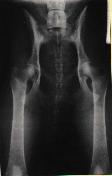

Na levém snímku můžeme vidět kyčelní klouby zdravého

zvířete, ale na druhém snímku je zrentgenované zvíře postižené těžkou

dysplazií.